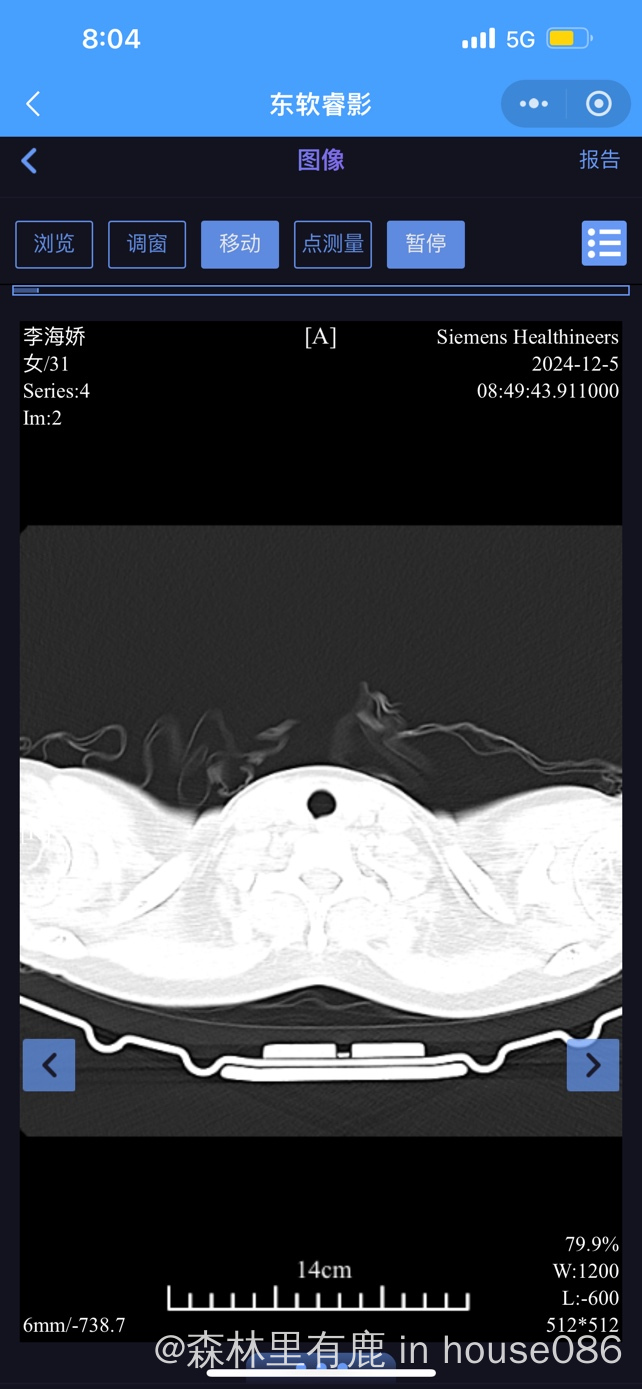

大家帮我看下胸部ct ,医生说右下肺叶很亚严重

现在也不知道是什么性质的肺炎,挂了几天抗生素,还每天会发烧几小时后才退烧